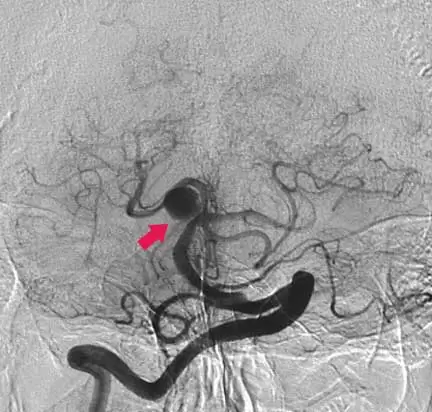

Un aneurisma cerebral es un ensanchamiento anormal en la pared de una arteria del cerebro. La mayoría de los aneurismas cerebrales no muestra síntomas hasta que se hacen grandes, filtran sangre o se rompen .